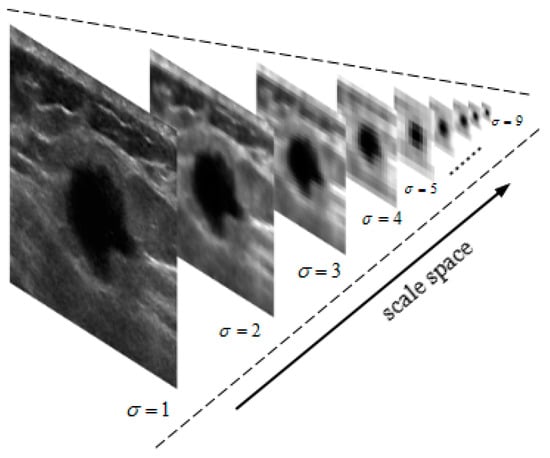

An Automatic Localization Algorithm for Ultrasound Breast Tumors Based on Human Visual Mechanism